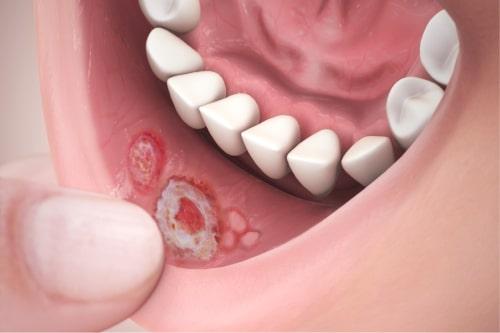

Stomatita aftoasă

Stomatita aftoasă (afte bucale) reprezintă apariția repetată a ulcerelor gurii la persoane care nu au alte afecțiuni. Cauza nu este complet înțeleasă, dar se crede că această afecțiune este un răspuns imunitar mediat de celule T, care este declanșat de o mulțime de factori. Ulcerele (afte) reapar periodic și se vindecă complet, deși în cazuri mai grave pot apărea noi ulcere în alte părți ale gurii înainte ca cele anterioare să se vindece. Stomatita aftoasă este una dintre cele mai obișnuite afecțiuni ale mucoasei orale și se crede că afectează, într-o oarecare măsură, 20% din populația generală.[4] Simptomele variază de la o mică pată colorată până la impactul asupra masticației, înghițirii și vorbitului, iar formele grave pot conduce la slăbire. Nu există leac pentru stomatita aftoasă, iar terapia urmărește reducerea durerii, a inflamației și ajutarea vindecării ulcerelor, dar sunt puține dovezi ale eficienței oricărui tratament care a fost folosit.